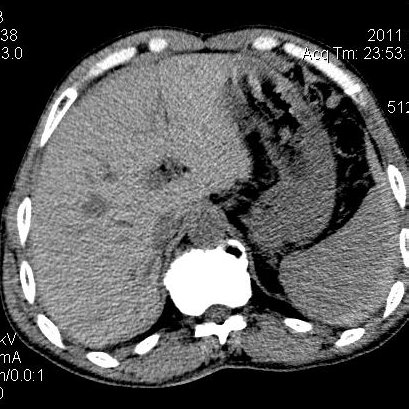

肝左叶发育异常

男性,55岁,骑摩托车摔倒后入院,自述右上腹疼痛

[backcolor=#FF0000]第一次诊断的时候也是这么肯定,可是床旁超声检查并没有发现明显异常,而且患者的一般症状都良好。还好临床只是保守治疗,没有立即手术,第二次复查的时候没有一点变化,又做了MRI检查,没有血肿,

这是一例肝左叶发育异常的,很个性吧~[/backcolor]